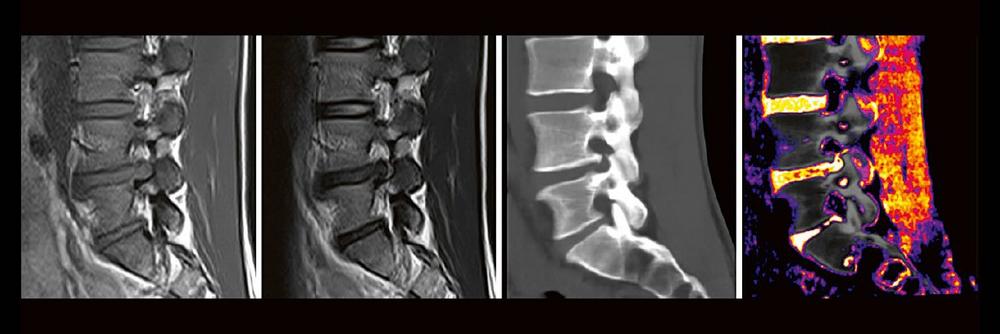

Die Dual-Energy-Computertomographie (DECT) hat für viele klinische Anwendungen bereits Einzug in die Praxis genommen. Für die Behandlung von Wirbelsäulenerkrankungen sind besonders die Darstellung von Knochenmarkveränderungen (z. B. bei osteoporotischen Frakturen) und der Bandscheibe (z. B. bei Bandscheibenvorfällen) interessant und werden intensiv beforscht. Hierdurch versprechen wir uns eine schnellere Therapie für unsere Patienten, weil viele Befund bereits in der CT erhoben werden können, die zuvor nur mit MRT sinnvoll abgebildet werden konnten. Darüber hinaus erhoffen wir uns wertvolle Zusatzinformationen bei degenerativen, traumatischen und entzündlichen Erkrankungen des Achsenskeletts.